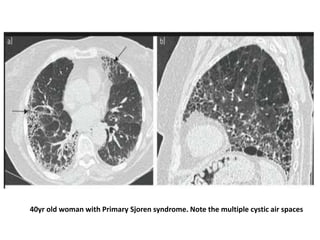

• Several histopathologic patterns have been described,

including NSIP, UIP, OP, and LIP

• LIP was considered one of the most common pulmonary

manifestations, but studies have demonstrated a much lower

prevalence. Its typical radiographic appearance is ground glass

opacities with thin-walled cysts

• Patients with SjS are at increased risk for pulmonary lymphomas

but clinically significant ILD is rare, and in most cases SjS-ILD

follows a mild and self-limited course

• Restrictive PFT and reduced DLCO have been found in 17%–

• Common radiographic findings are ground glass opacities

(45%-92%) and fibrotic honeycomb cysts (13%-43%)

• The presence of multifocal cysts on HRCT scan should

raise clinical suspicion for Sjögren-ILD

40yr old woman with Primary Sjoren syndrome. Note the multiple cystic air spaces